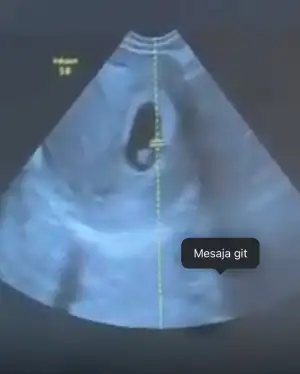

• 53346978-644f-4275-ac0d-5dde147cffcf.webp

53346978-644f-4275-ac0d-5dde147cffcf.webp

21,3 KB · Görüntüleme: 35

Kızlar benimkinide tahmin edin yaa kese yuvarlakmı ovalmi ben anlamıyorum burda 6+4 😂😂